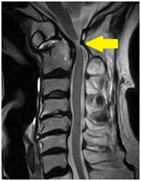

E頸椎の亜脱臼(10〜30%)

環軸椎が不安定で、脱臼を起こしやすい。

頸椎の第1番目の環椎が前方へずれる不安定な状態があると、脊髄(せきずい)が圧迫・損傷されて、

脊髄麻痺症状が出現します。

軸椎不安定性が有るときには、頸椎の亜脱臼に注意をします。

枕を入れたりしないで、頭や首を前にまげないようにします。

環軸椎(亜)脱臼のリスクが高いため、頭や首を前屈したり、頸椎に強い衝撃を加えないよう注意して下さい。